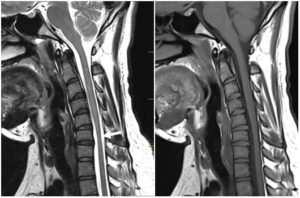

Hirayama disease is a form of motor neuron disease characterized by weakness & wasting of distal upper extremity effecting C5 to T1 level with predominant involvement of C7-T